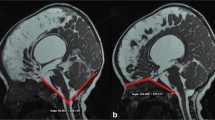

In this retrospective study, we included patients with MMC treated at our department from April 2006 to July 2023. All patients received head and spinal CT imaging after birth and underwent postnatal repair at our department. We specifically analyzed the initial head CT conducted immediately after birth. Before or after the repair surgeries, all cases underwent head and lumbar magnetic resonance imaging (MRI) to assess syringomyelia and Chiari malformation type II.

Quantitative assessment of intracranial volume (ICV), lateral ventricles volume (LVV), choroid plexus volume (CPV), and posterior cranial fossa volume (PCFV) in MMC patients used MATLAB R2023a (MathWorks, Natick, MA, USA) with digital imaging and communication in medicine (DICOM) CT data obtained immediately after birth. The target areas were manually segmented using the image segmenter app in MATLAB (https://www.mathworks.com/help/images/ref/imagesegmenter-app.html). Representative segmentation of ICV, LVV, CPV, and PCFV are shown in Fig. 1. Volume calculations (in milliliter, mL) were performed, and this method aligns with our previous studies [12,13,14,15]. LVV represented the volume of bilateral ventricles, and choroid plexus at the lateral ventricles and the foramen of Monro were assessed.